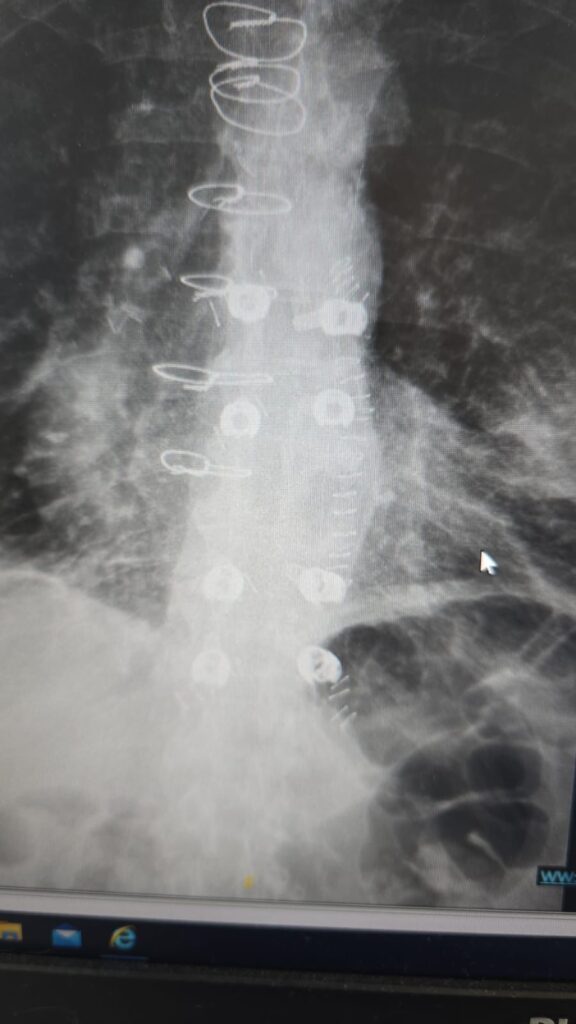

המטופל, גבר בן 60 שחלה בסרטן ריאה שפיתח גרורה בעמוד השדרה, הגיע למיון אסותא אשדוד כשהוא בסכנת שיתוק מיידית. במהלך הניתוח הוחדרו 8 ברגים ומוטות מקרבון בחיתוכים של כ־1 ס”מ בלבד, ובמקביל נכרת הגידול שגרם ללחץ על חוט השדרה. התוצאה הייתה דרמטית:

הטכניקה להכנסת ברגים בעמוד השדרה דרך חתכים זעירים אינה חדשה. למעשה, היא קיימת כבר כ־30 שנה ומשמשת בעיקר לטיפול בשברים בלתי יציבים. השיטה מבוססת על החדרת מחט לתוך החוליה בהנחיית שיקוף, הכנסת תיל מתכת עדין, הברגת הבורג למקומו המדויק, ולבסוף הכנסת מוט דרך אותם חתכים. השיטה מאפשרת ניתוח כמעט ללא דימום, זיהום מינימלי והחלמה מהירה.

להחליף את המתכת בברגים ומוטות מקרבון, חומר בעל מאפיינים פיזיקליים מורכבים שלא אפשרו לו עד כה לשמש בקיבוע עמוד שדרה בשיטה זעיר־פולשנית.

חברת CarboFix הישראלית היא זו שהצליחה לפצח את האתגר. בזכות הפיתוח החדש, ניתן כעת לשלב את הטכנולוגיה הזעיר־פולשנית המוכרת עם שתל מקרבון — ולפתוח דלת טיפולית חדשה לחלוטין לחולים אונקולוגיים.

ברגים ומוטות מקרבון אינם יוצרים הפרעות בהדמיות MRI, ומאפשרים לבצע בדיקות איכותיות גם לאחר הניתוח. בנוסף, הם מפחיתים משמעותית סיכונים בהקרנות-ומאפשרים לרופא האונקולוג לכוון את הקרינה בדיוק רב יותר.